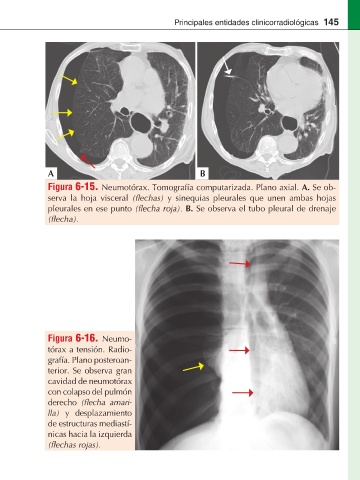

Figura 6-15. Neumotórax. Tomografía computarizada. Plano axial. A. Se ob-

serva la hoja visceral y sinequias pleurales que unen ambas hojas

pleurales en ese punto B. Se observa el tubo pleural de drenaje

Figura 6-16. Neumo-

tórax a tensión. Radio-

grafía. Plano posteroan-

terior. Se observa gran

cavidad de neumotórax

con colapso del pulmón

derecho -

lla) y desplazamiento

de estructuras mediastí-

nicas hacia la izquierda